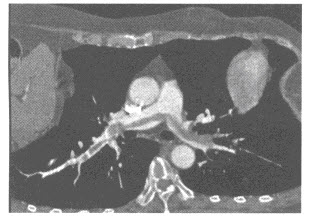

患者女性,52岁。呼吸困难1个小时。CT肺动脉造影如下图,应诊断为()

A.急性肺动脉栓塞

B.慢性肺动脉栓塞

C.肺动脉高压

D.肺动脉损伤

E.肺动脉狭窄